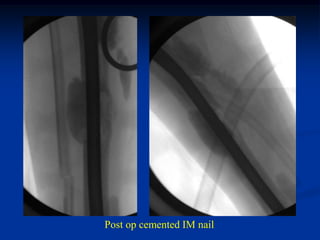

Case #1144

55 year female with

metastatic lung CA

to distal tibia